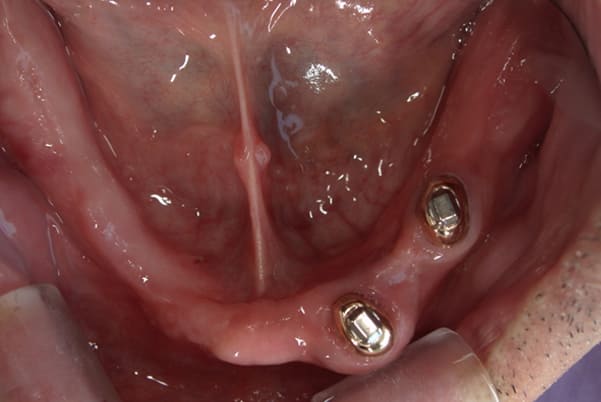

治療後に入れ歯を外した上顎

-

治療後に入れ歯を装着した上顎

治療後に入れ歯を外した下顎

治療後に入れ歯を装着した下顎